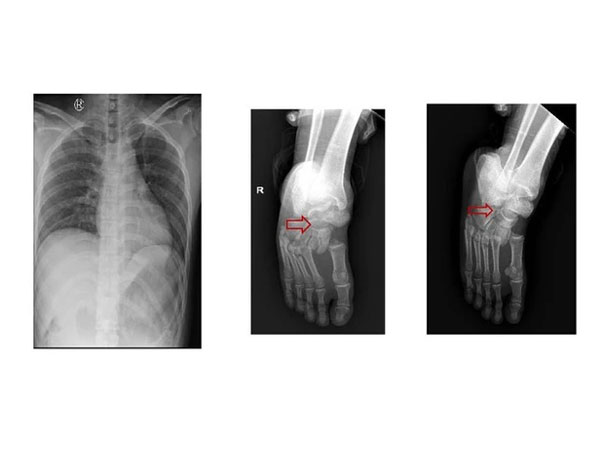

Nam công nhân gãy hết xương sườn phải, cụt sát nách vì cuốn tay vào băng chuyền sản xuất

Khoa Hồi sức tích cực - Chống độc, BV Đa khoa tỉnh Phú Thọ vừa cứu sống thành công trường hợp một công nhân bị cuốn vào băng tải dây chuyền dẫn đến cụt một bên tay phải.